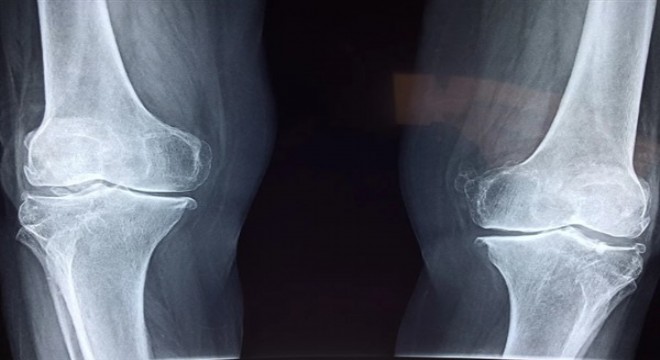

Yaş, yaralanma ya da çeşitli hastalıklar kalça eklemlerinin yıpranmasına sebep olabiliyor.

Yıpranmış kalça eklemleri hareket etmek, yürümek ve oturup kalkarken ağrıya neden olabiliyor. Zaman içinde kişinin hareket kabiliyeti de azalıyor, bu sebeple kalça eklemine protez ameliyatı gerekli olabiliyor. Ancak erken teşhis ile gerekli önlemleri alınarak, hasta güçlü bir eklem yapısına kavuşabiliyor. Memorial Antalya Hastanesi Ortopedi ve Travmatoloji Bölümü’nden Prof. Dr. Ahmet Turan Aydın, kalça kireçlenmesi ve erken teşhisin önemi hakkında bilgi verdi.

Basit bir kalça filmi erken teşhisi mümkün kılar

Kalça ekleminde hissedilen ağrıda yapılan özel testlerle hastanın belli hareketleri yapıp yapamadığı incelenir. Kalça filmi kalçanın yapısında bozukluk olduğunu gösteren çok önemli ayrıntıları ortaya koyabilir. Böylelikle tedavisi mümkün olmayan, kişiyi protez ile yaşamaya mahkum bırakan bir hastalık olan kireçlenmeye doğru gidebilecek bir tablo, çok önceden tespit edilerek gerekli önlemler alınabilir.